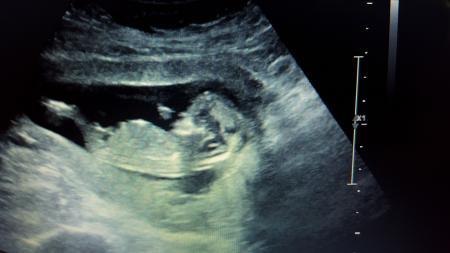

Ich habe noch ein zweites Bild

Ich sehe da garnichts. Ist es nicht viel zu früh für EIN Outing??? Mein Sohn sah sehr lange aus wie ein Mädchen.